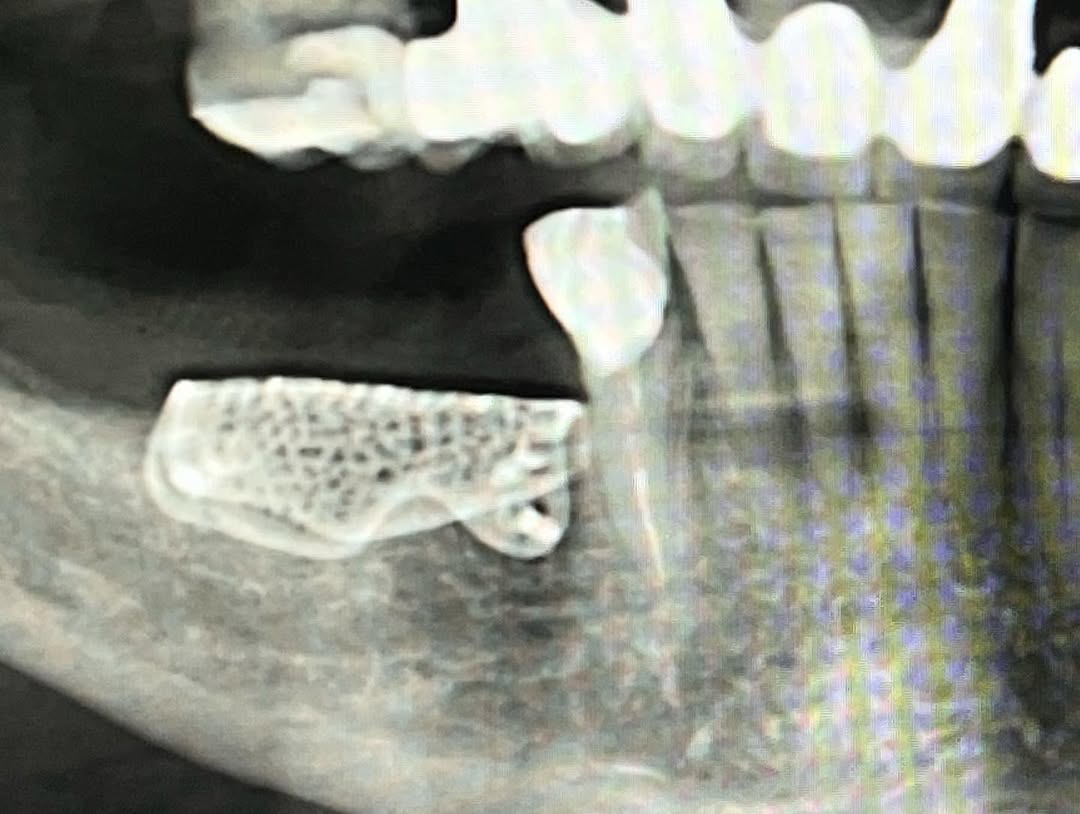

...Se presenta un caso clínico de restauración directa en resina composite, ejemplo del valor de la precisión y la técnica meticulosa incluso en procedimientos considerados rutinarios dentro de la práctica diaria. El caso pone en evidencia la importancia del control de la morfología, la textura y la integración cromática, así como del adecuado aislamiento del campo operatorio y la estratificación del material, factores determinantes para conseguir un resultado natural, funcional y duradero. A través de una ejecución cuidadosa, se logró una restauración estéticamente imperceptible y funcionalmente estable, que respeta los principios de mínima invasión y adhesión efectiva. Este tipo de procedimientos, aunque cotidianos, reflejan la constancia y el nivel de exigencia clínica necesarios para ofrecer odontología de calidad en todos los casos, independientemente de su complejidad.